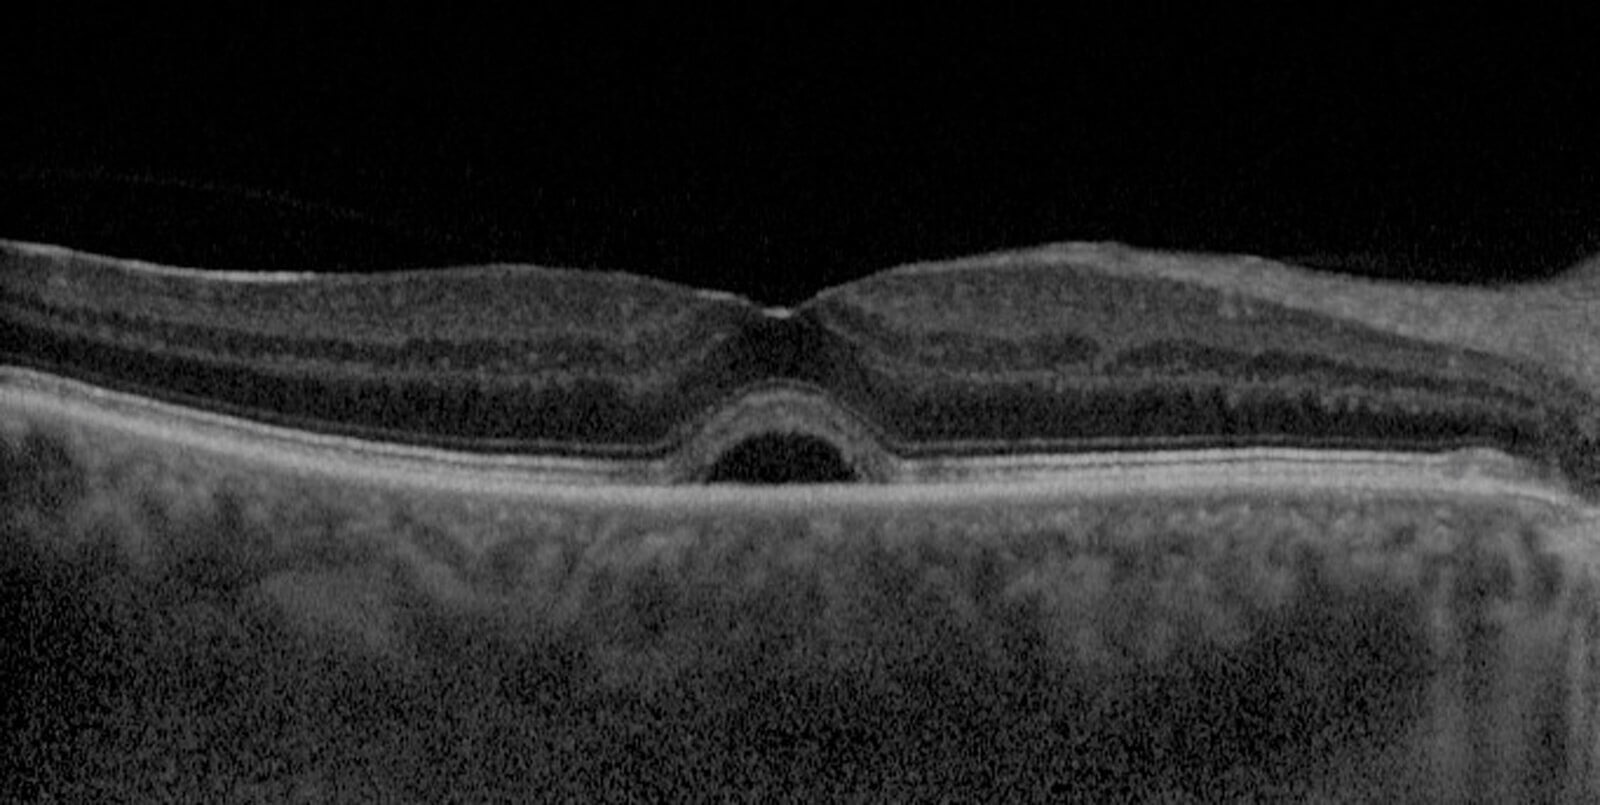

Figure 3: SD-OCT scan of subretinal fluid.

Subretinal fluid: Space of separation of the neurosensory retina from the RPE.